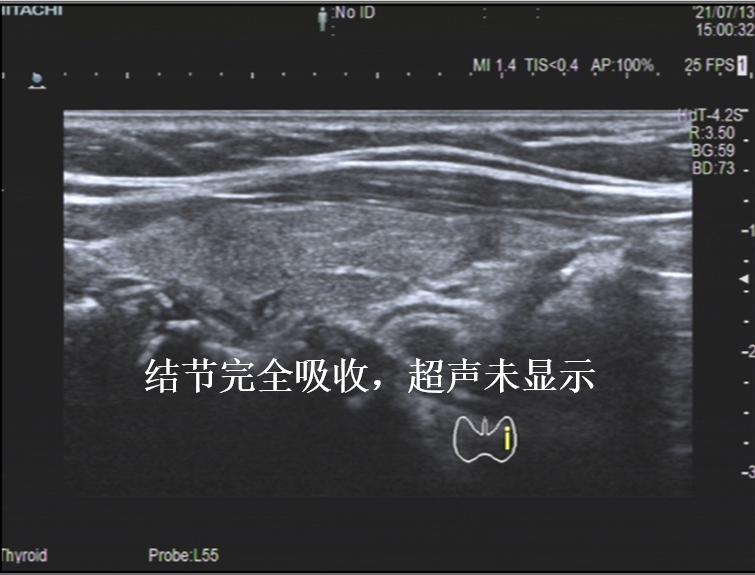

病例③: 25mm的甲状腺结节微创消融后1年半,完全吸收

微创消融前后超声对比,结节完全消失